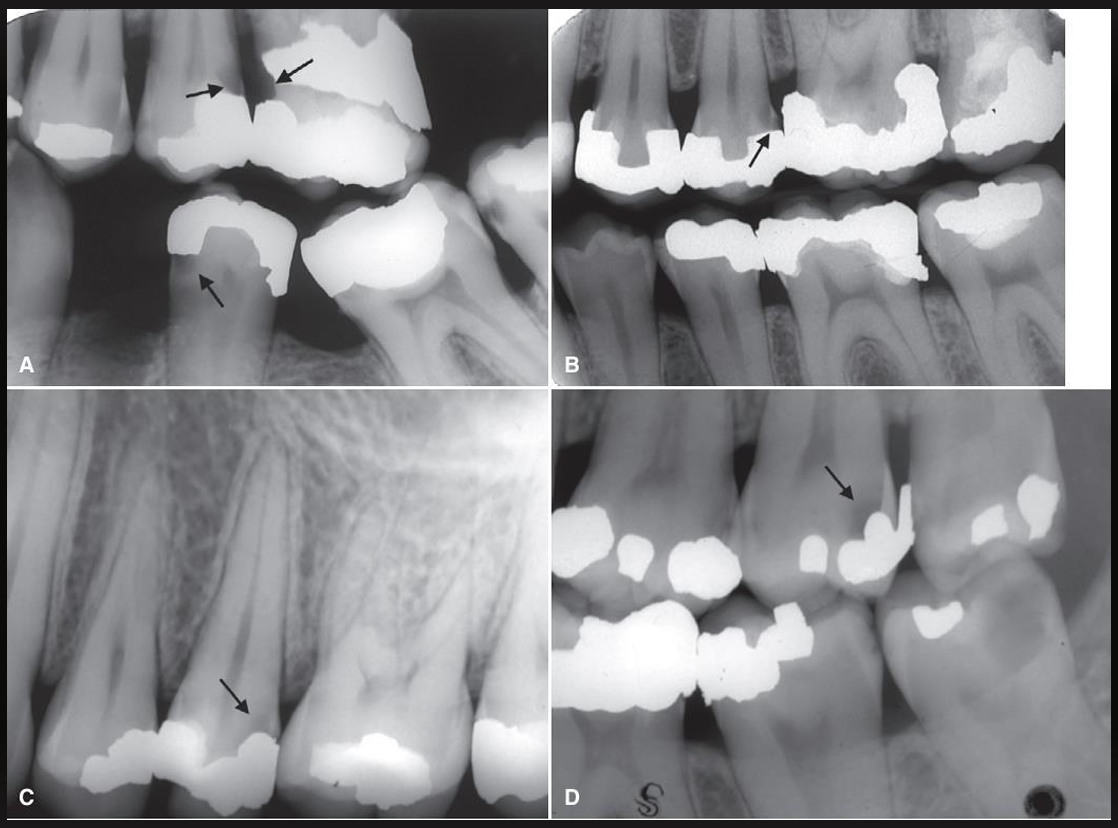

what are these?

large occlusal caries

small occlusal caries

radiographs are not very effective at detecting, may be seen as thin radiolucent line or cup shaped zone underlying occlusal enamel

minimum or no changes in enamel

what are these arrows pointing at? (except for 2nd molar in image D)

what do these images have?

recurrent caries

what are these arrows pointing at?

a restoration with a radiolucent liner- the box is too sharply defined to be a natural process (like secondary caries)